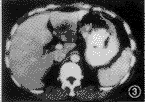

1.临床疗效判定: 栓塞前CT平扫见有低密度区域,增强见典型“早出晚归”现象。DSA显示早动脉期即出现边界锐利的点状血窦,沿瘤体周边分布,随时间推移,瘤体染色自外周向中心扩展,边界变得模糊,血窦染色排空明显延迟。注入PLE后6例CHL肿瘤血窦均明显染色(图1,2)。栓塞后1~6个月CT平扫见瘤体内碘油沉积,肿瘤直径明显缩小(图3,4)。栓塞前肿瘤直径平均为(6.8±1.5) cm,栓塞后平均为(2.5±2.1) cm。栓塞前后肿瘤直径经t检验,有显著性差异(t=4.485,P<0.05)(表1)。

图3 栓塞前CT增强扫描见肝左叶低密度影,长径为5.0 cm